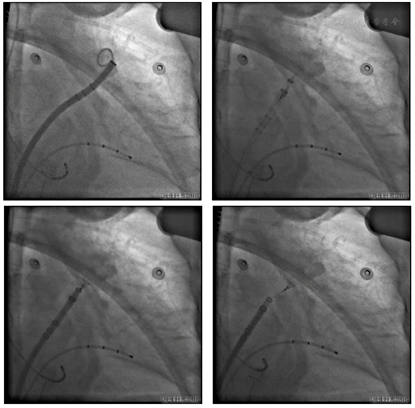

穿刺成功先行房颤射频消融治疗,消融完成后更换左心耳封堵鞘,以猪尾导管保护于RAO30° CAU25°造影,左心耳形态充分暴露,可以观察到心耳属于反鸡翅形状。内部梳状肌较发达,深度较浅。DSA测量开口18mm,深度19mm,与CT测量结果类似,考虑选择24mm watchman封堵器,首选X3轴向进行封堵。术中在猪尾导管的保护下,逆时针旋转输送鞘,尽量将输送鞘送入上叶。稳定输送系统,体外预借2mm深度,送入封堵伞,逆时针旋转稳定输送鞘,术中缓慢释放封堵伞,释放后稳定5分钟后造影提示封堵完全,上缘轻度露肩,行TEE检查未见残余分流,压缩比测量12.5%~21%(图7,图8),经牵拉测试稳定,符合PASS原则,决定释放封堵器,释放后再次造影提示封堵完全(图9)。术后患者顺利清醒,术后6小时检测无心包积液,加用达比加群110mg 2次/天;术后第五天出院。